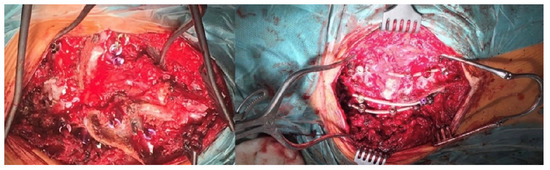

After a thorough orthopedic examination and additional tests (X-ray, MRI of the entire spine, CT), and consultations with other specialists, including a cardiologist, pulmonologist, neurologist, and neurosurgeon, the five-year-old female pediatric patient with congenital scoliosis and severe kyphoscoliosis qualified for surgical treatment of the spinal deformity via a posterior approach with three-column osteotomy and fusion (Figure 1).

Neurological examination before the surgical treatment indicated neurological function was intact. MRI and CT performed before the surgery showed multilevel mixed congenital spinal anomalies in the cervical and thoracic spine, without spinal cord pathologies (hemivertebrae, blocked vertebrae, Figure 2 and Figure 3).

Figure 1. Standing X-rays of the five-year-old girl before surgical treatment.